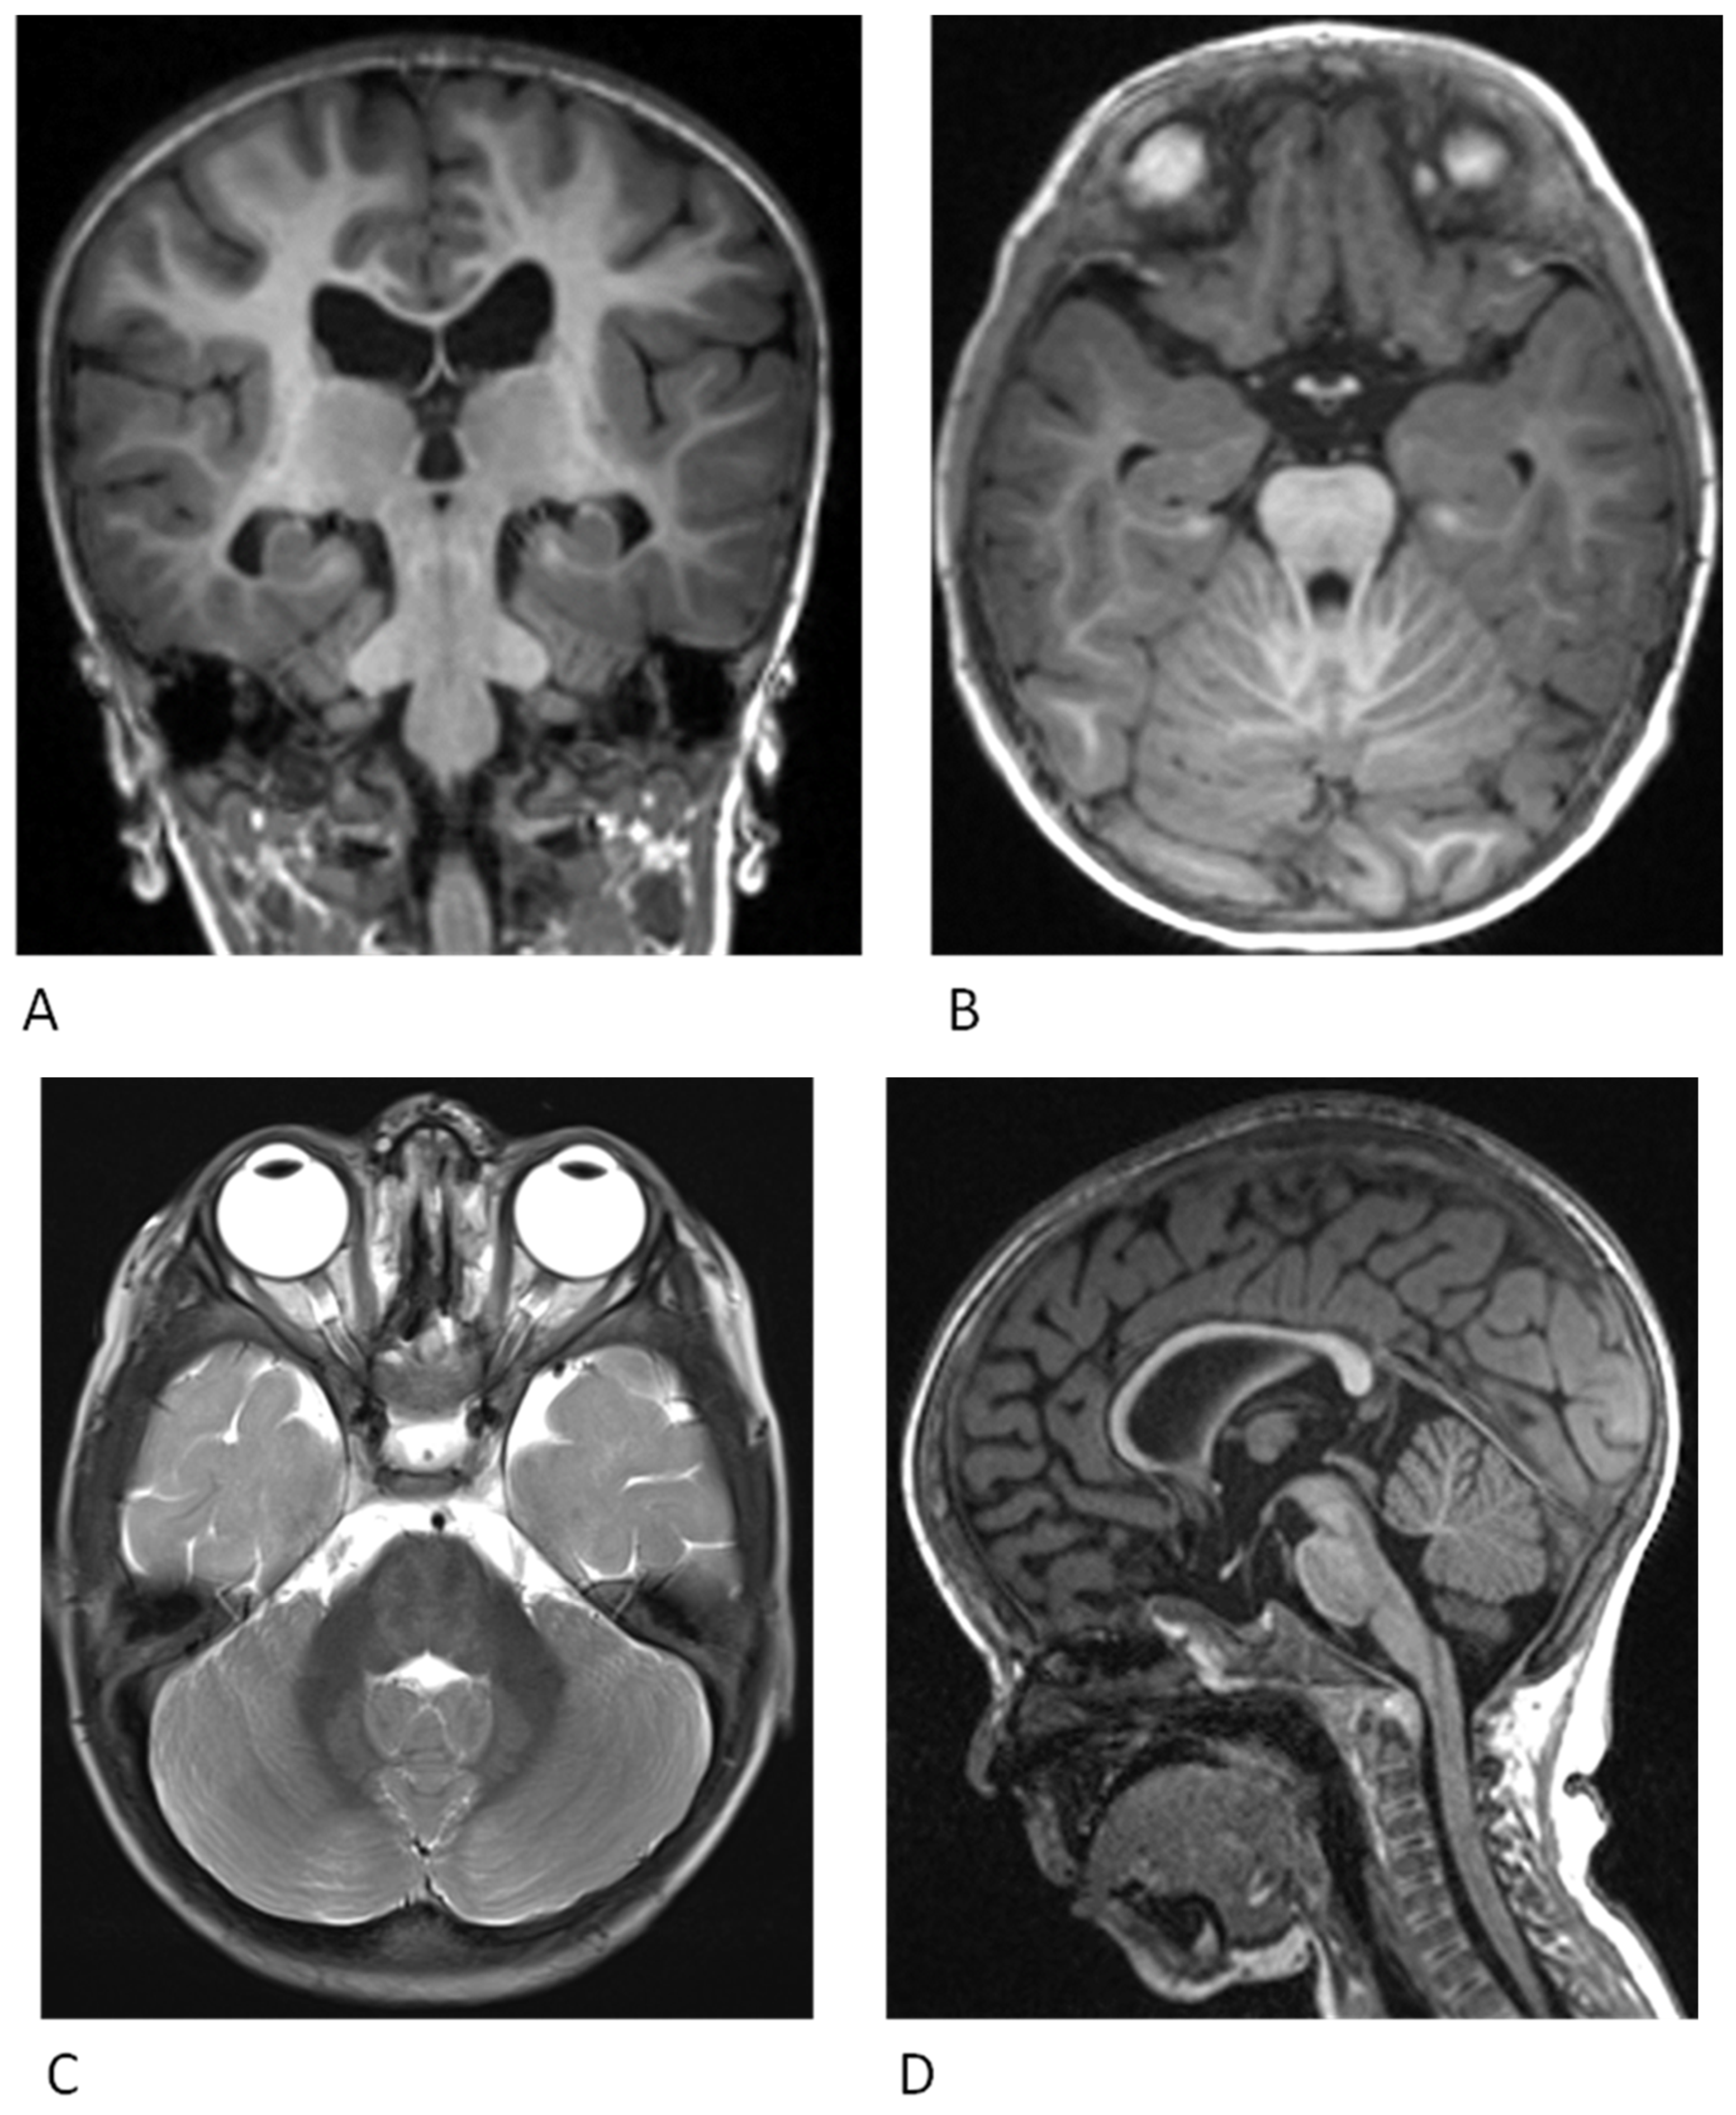

4. Neurological Findings

- Papadopoulou, E.; Sifakis, S.; Sol-Church, K.; Klein-Zighelboim, E.; Stabley, D.L.; Raissaki, M.; Gripp, K.W.; Kalmanti, M. CNS imaging is a key diagnostic tool in the evaluation of patients with CFC syndrome: Two cases and literature review. Am. J. Med. Genet. A 2011, 155, 605–611. [Google Scholar] [CrossRef]

- Weaver, K.N.; Gripp, K.W. Central nervous system involvement in individuals with RASopathies. Am. J. Med. Genet. C Semin. Med. Genet. 2022, 190, 494–500. [Google Scholar] [CrossRef]